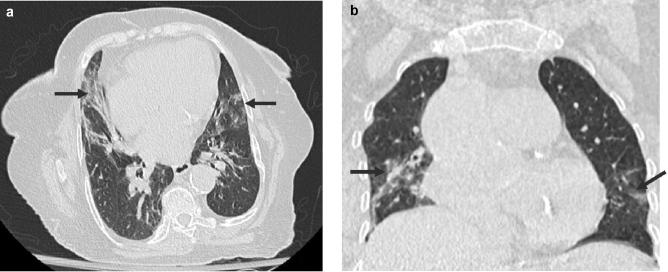

The typical HRCT findings were seen in 50 scans (65.8%) out of total positive ones; 44 (77.2%) with positive RT-PCR results and 6 (31.6%) with negative results. The peripheral disease distribution was seen in 86%, multilobe involvement in 70%, bilateral in 82%, and posterior in 82% of the 50 scans. The ground glass opacities were seen in 50/74 (89.3%) of the positive RT-PCR group. The recognized GGO patterns in these scans were: rounded 50%, linear 38%, and crazy-paving 24%. Using RT-PCR as a standard of reference, chest HRCT scan revealed a sensitivity of 68.8% and specificity of 70%.

The commonest HRCT findings in patients with COVID-19 pneumonia were peripheral, posterior, bilateral, multilobe rounded ground-glass opacities. The performance of HRCT scan can vary depending on multiple factors.

在所有阳性扫描中,50次扫描(65.8%)出现典型的HRCT表现;RT-PCR结果阳性的有44次(77.2%),阴性的有6次(31.6%)。在50次扫描中,86%的病例出现外周病变分布,70%出现多叶受累,82%为双侧受累,82%为后部受累。在RT-PCR阳性组的74例中,50例(89.3%)出现磨玻璃影。这些扫描中公认的磨玻璃影模式为:圆形占50%,线性占38%,铺路石样占24%。以RT-PCR作为参考标准,胸部HRCT扫描的敏感性为68.8%,特异性为70%。

新冠肺炎肺炎患者最常见的HRCT表现为外周、后部、双侧、多叶圆形磨玻璃影。HRCT扫描的性能可能因多种因素而异。